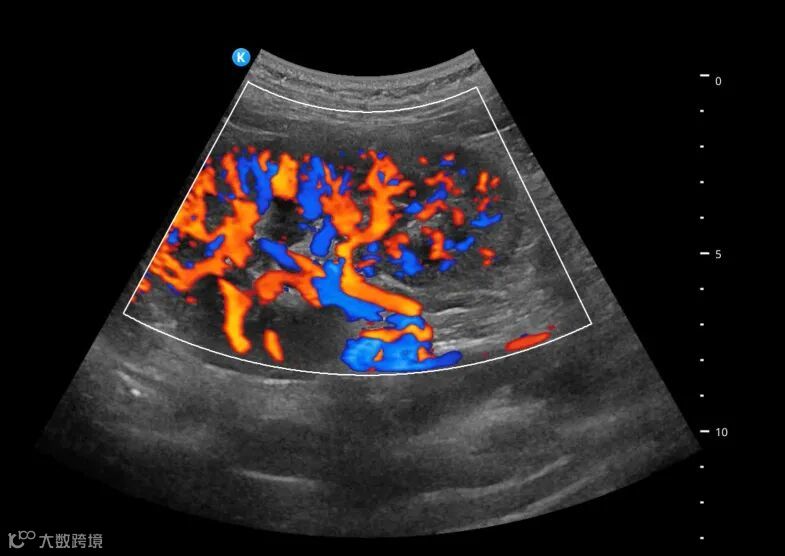

深圳鲲为科技有限公司是以突破性原创技术引领,并致力于下一代超分辨超声开发的专业影像设备公司。